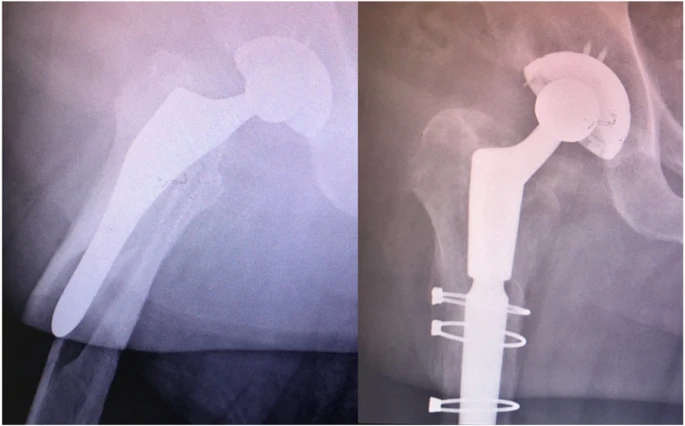

1. Переломы VancouverB2 подразделяются на четыре различных типа переломов: ранее описанный оскольчатый «взрывной», грейферный и спиральный, а также недавно наблюдаемый «обратный» грейферный.Представлен репрезентативный рентгеновский вид серии и соответствующее графическое изображение (рис. 1).

2. Взрывные и спиральные переломы были в значительной степени связаны с цементированными ножками, тогда как переломы лоскута были в значительной степени связаны с нецементированными ножками.

3. Обратная раскладушка произошла одинаково в обоих стеблях.

4. Связь подтипов Ванкуверской классификации, включая четыре типа переломов B2, описанных выше, с геометрией ножки отражает общую тенденцию типов переломов.

Перелом Ванкувера B2